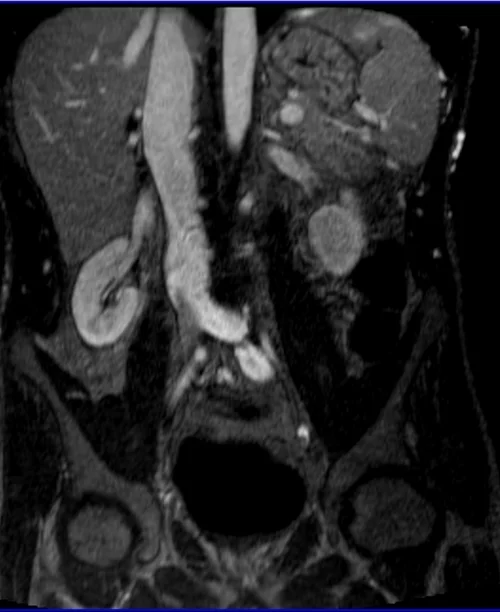

MRA Renal Arteries